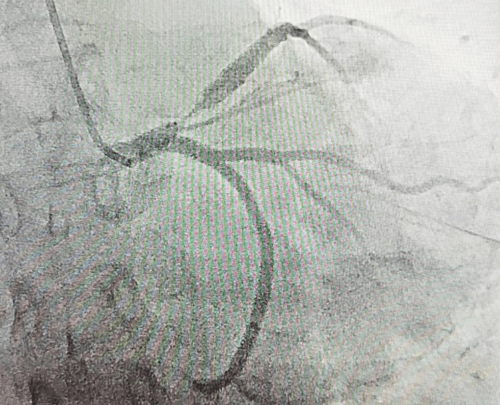

冠脉手术后